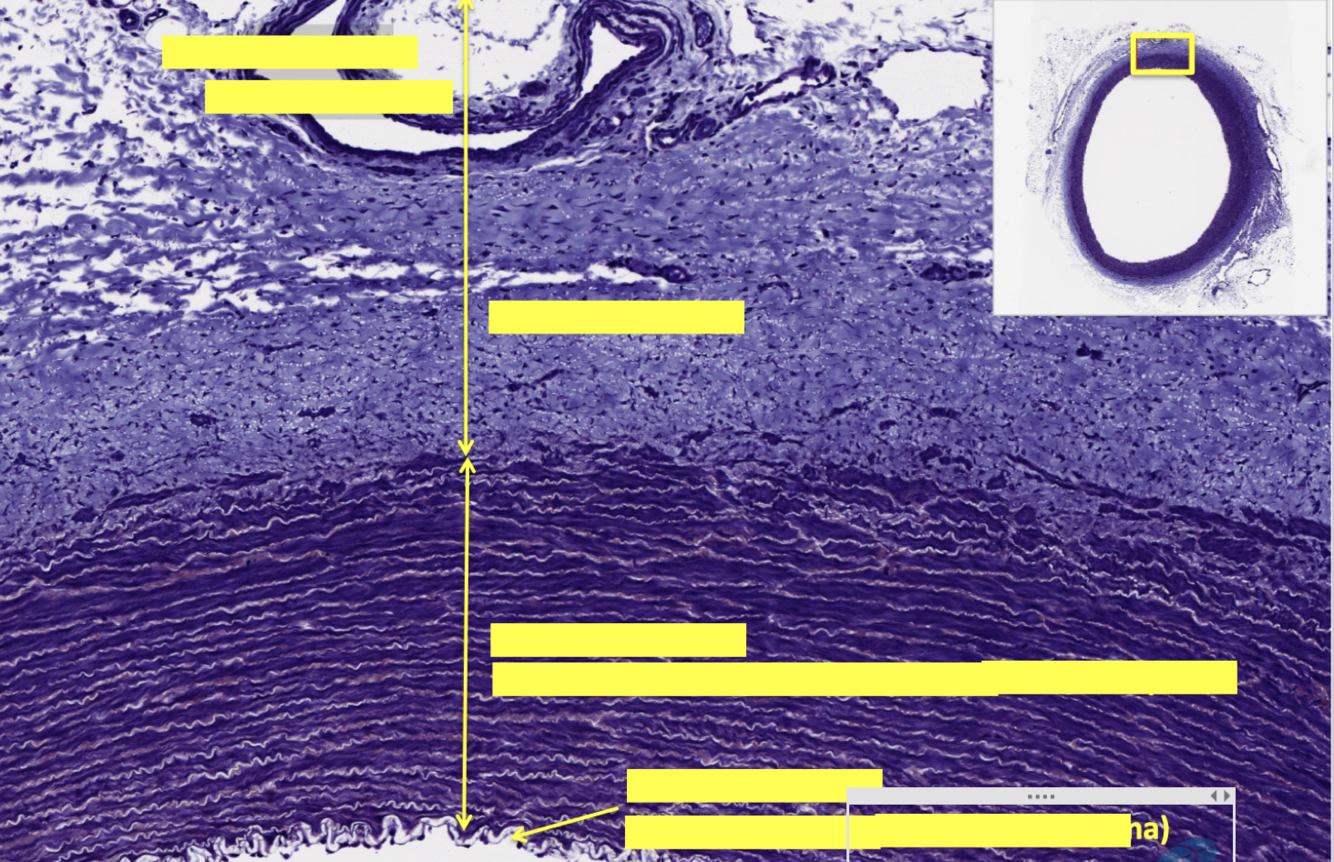

top layer

middle layer

bottom layer

epicardium

myocardium

endocardium

endocardium is composed of what cells?

what is between the two arrows?

intercalated disc